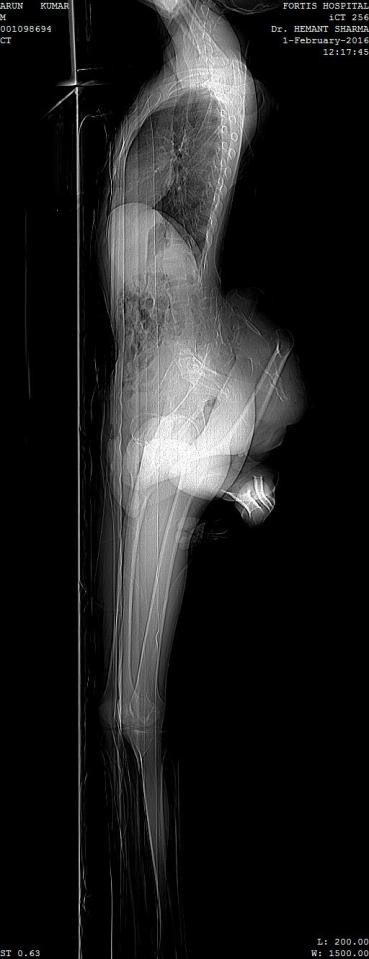

Bác sĩ Hermant Sharma – người làm xét nghiệm cho Arun - đã phát hiện ra chàng trai này còn có một xương chậu thứ 2. Bên cạnh đó, bác sĩ Hermant còn tiến hành một loạt hình thức chụp chiếu để kiểm tra xem cặp chân thừa của Arun mọc ra chính xác từ đâu và nó phát triển bằng cách nào?